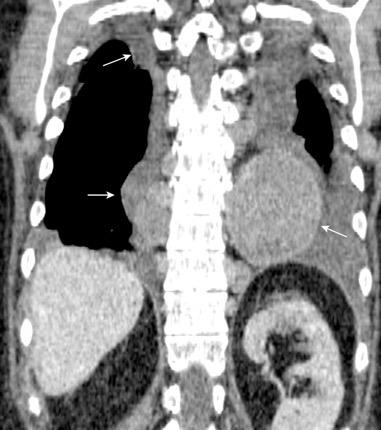

Líneas paraespinales formando un “paréntesis” por encima del diafragma. El signo señala el origen “intratorácico” de la lesión.

Conrad A et al. Pott’s disease associated with large and multiple abscesses in a 30-year-old migrant from Chad. BMJ Case Rep 2018

(lesiones toracoabdominales) La divergencia de las líneas paraespinales apunta a lesión toracoabdominal, que desde el tórax desciende y penetra en el abdomen.

Signo del “iceberg” positivo en Tb vertebral

Afectación por vía hematógena. Región dorsolumbar más frecuente. Afectación inicial: irregularidad de los platillos vertebrales, disminución del disco intervertebral con esclerosis ósea adyacente. Kim. Radiographics.2001